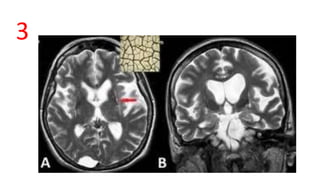

PUTAMINAL SLIT SIGN

• T2 W axial

• MSA-P - lateral margin of putamen

• T2 hyperintensity - due to severe atrophy of putamen and enlargement of space

between putamen and external capsule

• Sensitivity ~ 97%

• Sometimes may be seen in Wilson disease also (young patients)